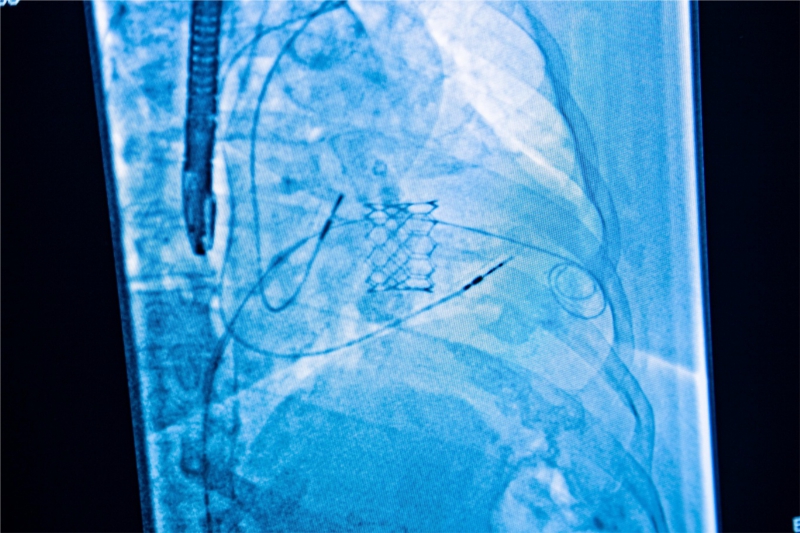

TAVI (Implantare Percutană de Valvă Aortică) reprezintă o procedură intervențională microinvazivă de schimbare a valvei aortice fără deschiderea toracelui, indicată în special pacienților în vârstă sau cu risc chirurgical crescut. MONZA ARES a realizat peste 500 de proceduri TAVI începând cu 2014, un record pentru mediul privat din România. TAVI reduce semnificativ, riscurile procedurale și timpul de recuperare, contribuind la rata de succes foarte mare a intervențiilor.

Intervenția TAVI este realizată fără deschiderea pieptului, pe cale arterială. Medicul cardiolog intervenționist face o mică incizie la nivelul plicii inghinale pentru a permite inserția în artera femurală a unui cateter prevăzut la capăt cu valva aortică nouă. După inserare, acesta este avansat până la nivelul inimii, sub control radiologic. Odată ajuns în dreptul valvei aortice, valva nouă este implantată la nivelul inelului aortic, unde este eliberată sub control radiologic și ecografic.